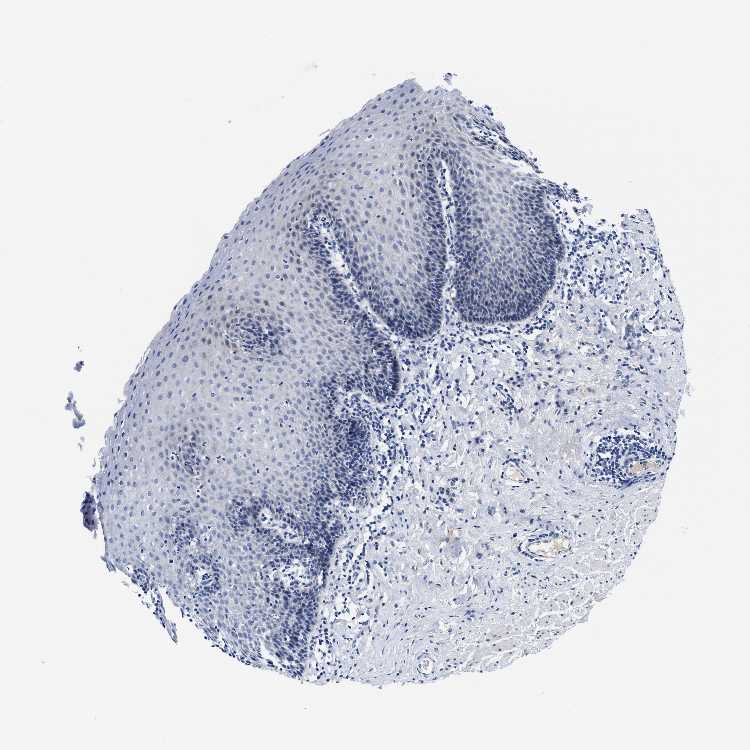

ESOPHAGUS - Antibody stainingi

Antibody staining in the annotated cell types in the current human tissue is reported as not detected, low, medium, or high, based on conventional immunohistochemistry profiling in selected tissues. This score is based on the combination of the staining intensity and fraction of stained cells.

Each image is clickable and will lead to virtual microscopy that enables deeper exploration of all samples and also displays staining intensity scores, fraction scores and subcellular localization as well as patient and tissue information for each sample.

Antibody HPA022991

Squamous epithelial cells Not detected